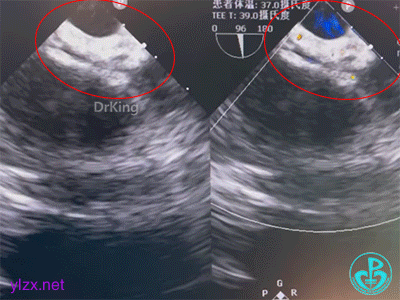

牵拉试验

牵拉试验时,封堵器形态稳定,形态未发生改变,判定锁定成功。

封堵成功

最后封堵器盘面稳定夹持房间隔,封堵器成型良好,未见分流,封堵成功。